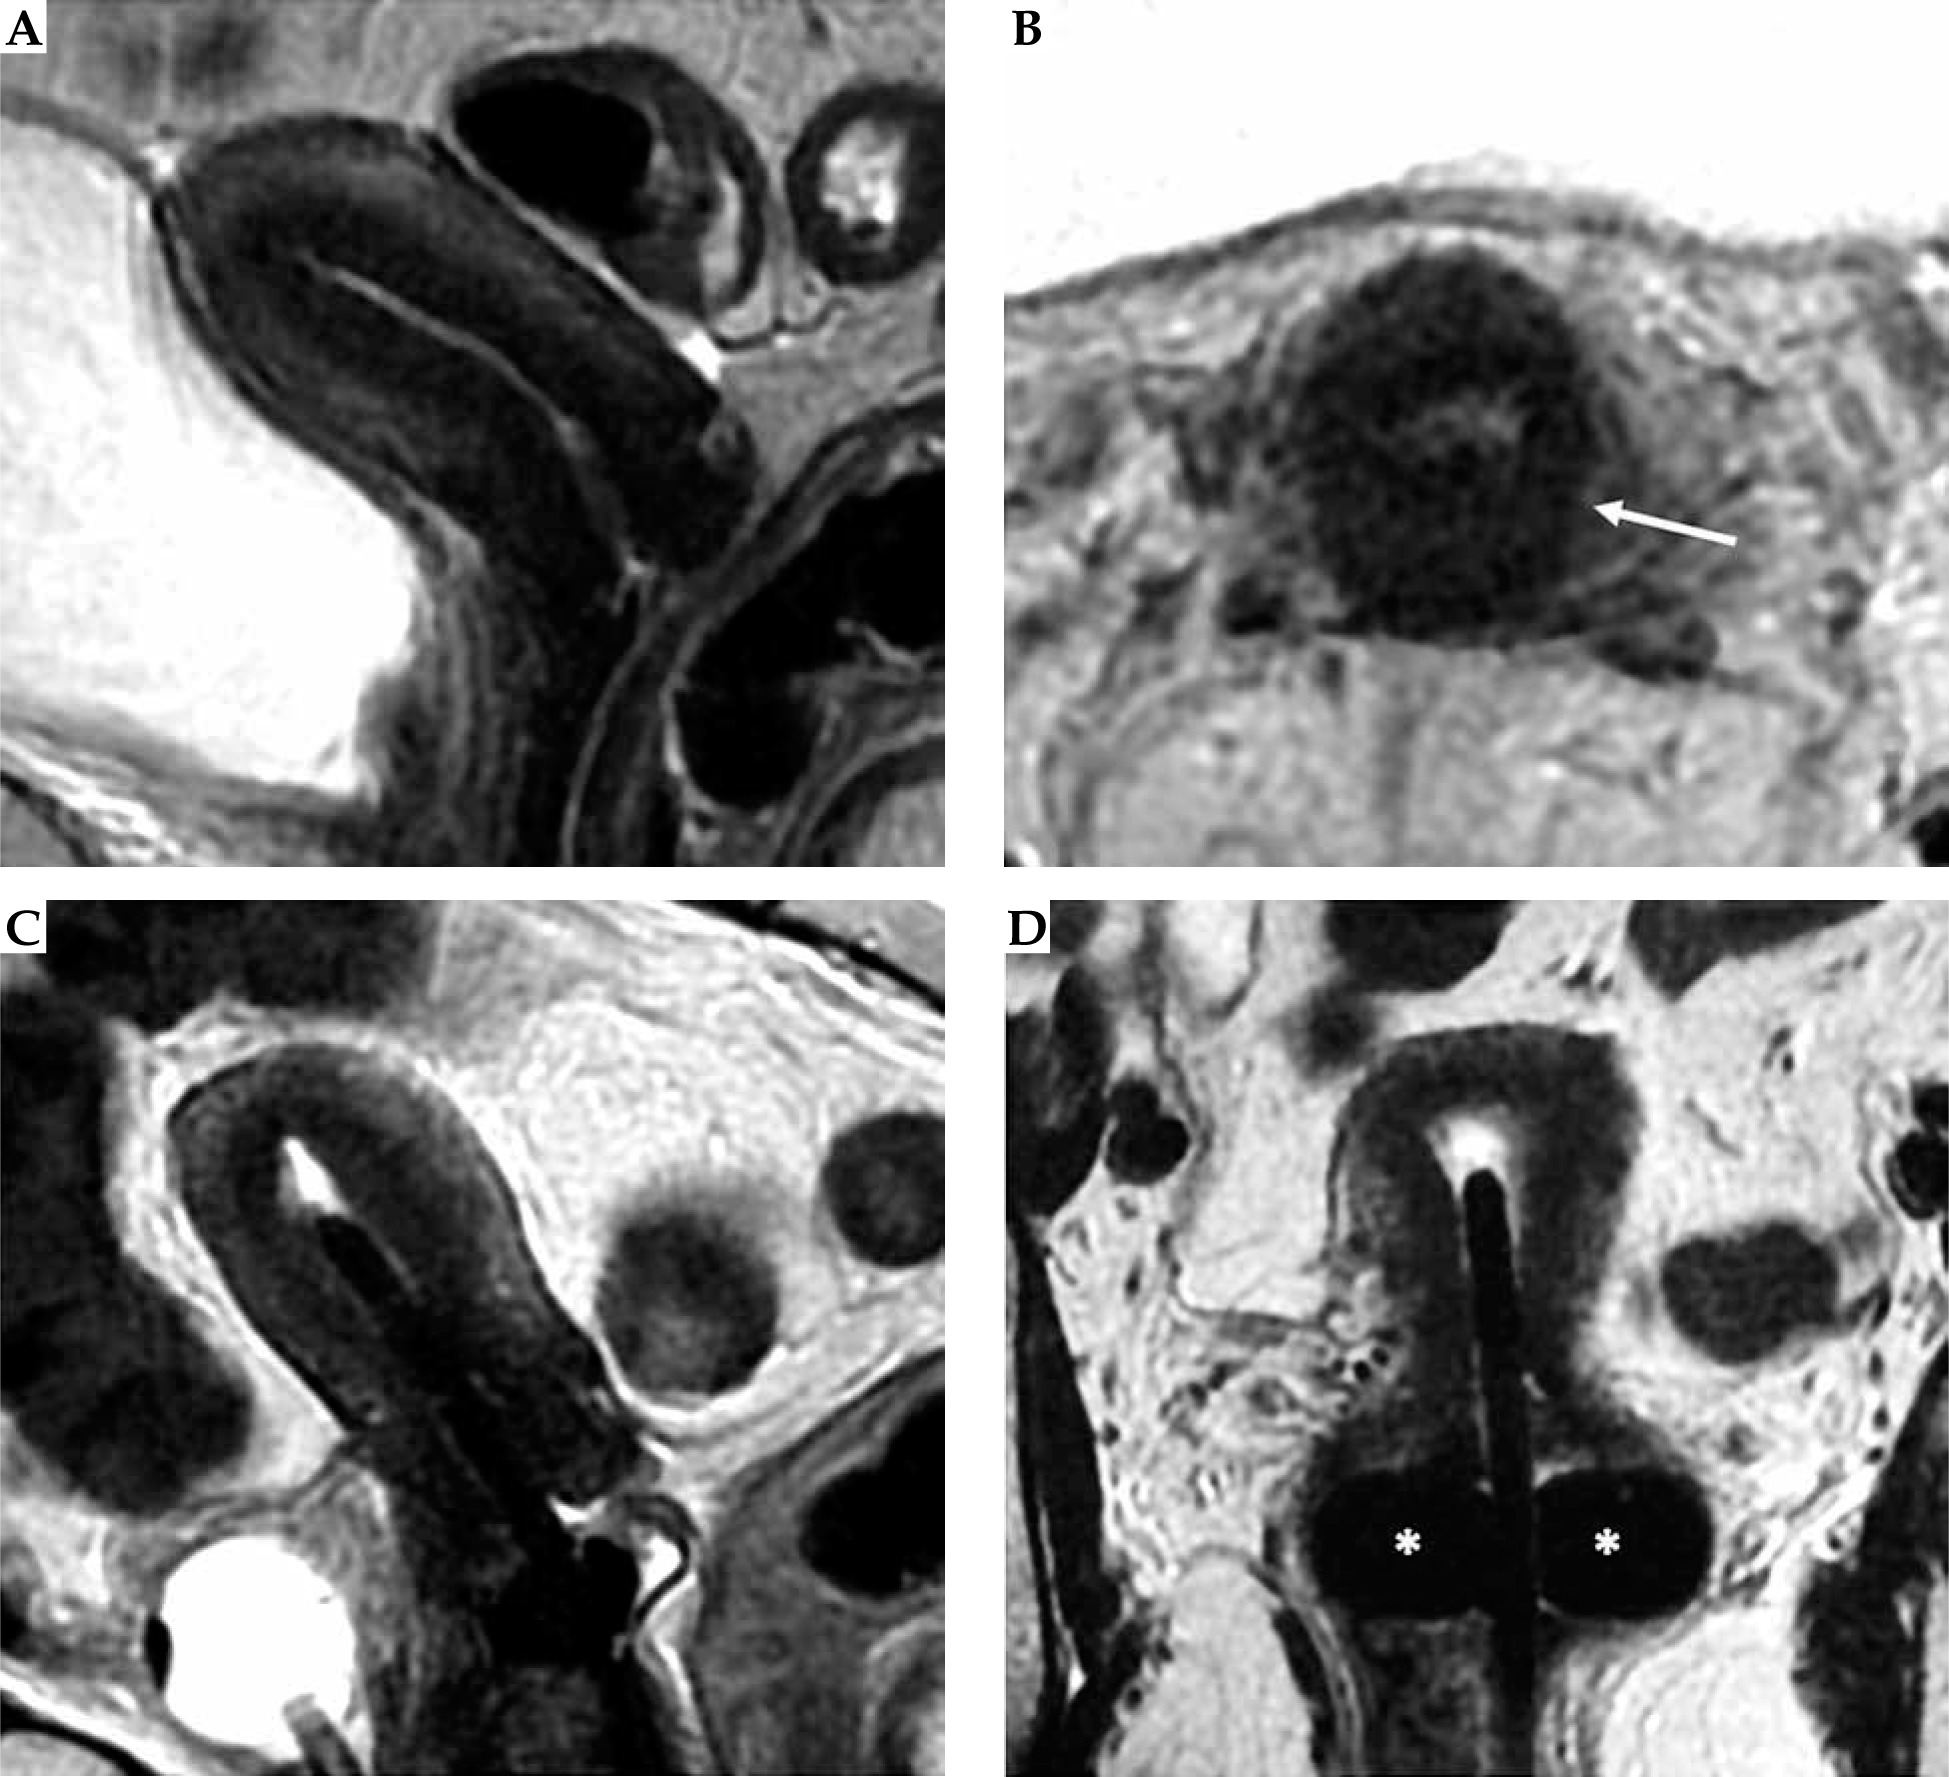

Fig. 3

Post-external beam radiotherapy (EBRT) recto-vaginal fistula. Baseline and post-EBRT MRI in 72-year-old woman with squamous cervical carcinoma. At baseline MRI (A, C), T2-w sequences show the hyperintense cervical mass, extending to the upper third of the vagina, with maximum diameter of 50 mm (any plane). After concurrent EBRT (B, D), T2-w sequences show the presence of an hyperintense area in the posterior wall of the cervix and posterior vaginal fornix. Post-EBRT MRI presents a rectovaginal fistula (arrow)

Fig. 11

55-year-old woman with squamous cell cervical carcinoma. Post-external beam radiotherapy (EBRT) coronal and axial oblique FSE T2-weighted images (A, B) show high signal-intensity residual tumor (T) in the right stromal portion and in the right vaginal fornix. Post-applicator coronal T2-weighted image (C) presents the relationship between the applicator and the residual tumor (arrow)